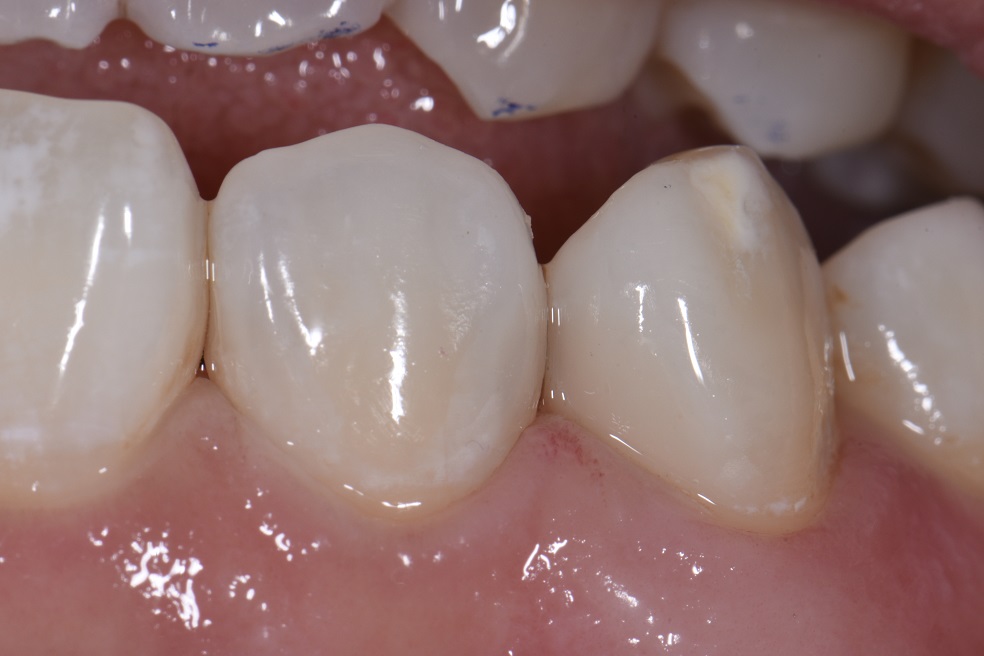

Dental Class 3 Restoration . Preparation outline is determined by the extent of the carious lesion, defects, or old restorative material. It is generally formed with. this paper aims to provide the dentist with practical guidance on the technique for direct composite restoration. dental restoration ranges in price, dependent on what type of restoration you require and which dental clinic you are visiting. in general, the tooth preparation for a class iii direct composite restoration involves (1) obtaining access to the defect (caries,. at first glance, a class iii direct composite restoration can appear to be a fairly routine procedure.